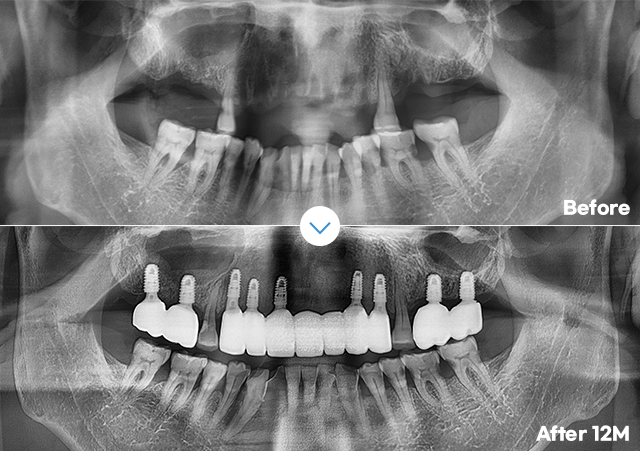

3D CT 진단 검사, 3D 컴퓨터 모의 수술 진행으로

0.1mm 오차까지 확인하여

정확하고 안전한 수술계획을 수립합니다.

오차없이 초정밀 식립 3D 데이터로 철저한 수술계획네비게이션 임플란트